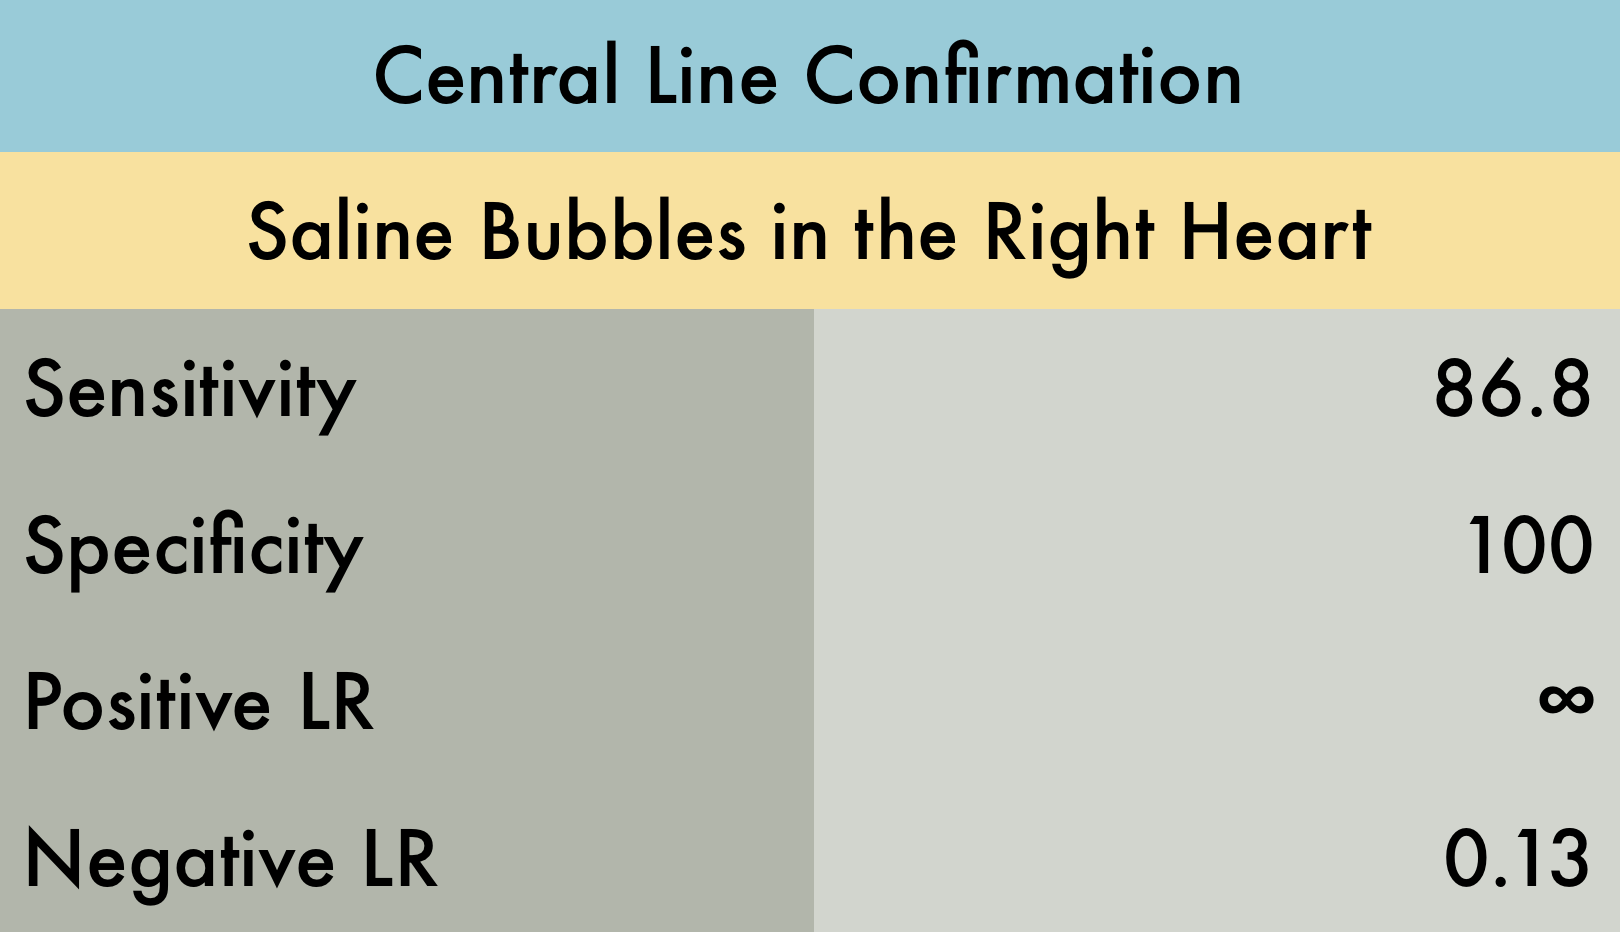

The Evidence Atlas: Procedures

Central Line Placement Confirmation

A central venous catheter was placed in the right internal jugular under ultrasound guidance and subxiphoid view was obtained. Saline was rapidly flushed through the brown port and turbulent saline can be seen traveling through the right side of the heart. - Dr. Matthew Riscinti and Dr. Isaac Gordon - Kings County Emergency Medicine